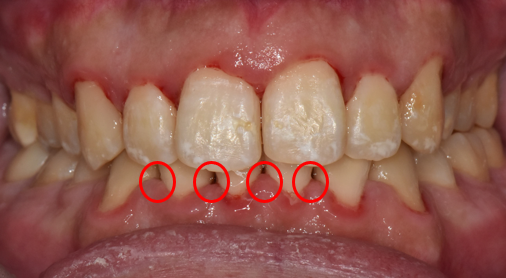

안녕하세요. 운정치과 15년 경력의 치과의사 대표원장 임희철입니다. 오늘 보시는 분들께 뿌리사랑치과에서 하셨던 분의 케이스 보여드리고 스케일링이라는 좋은 정보를 알려드리면 스케일링을 왜…